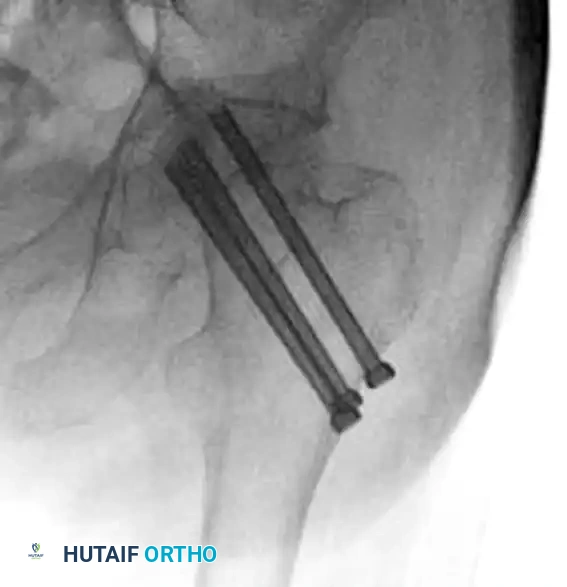

While osteonecrosis (avascular necrosis) is classically associated with intracapsular femoral neck fractures, proximal femoral trauma and its subsequent surgical management can occasionally compromise the vascular supply to the femoral head, particularly in combined fracture patterns or following aggressive surgical dissection.

FIGURE 55-19 Osteonecrosis after treatment of proximal femoral fracture. Anteroposterior radiograph (A), axial CT scan (B), and coronal CT scan (C) demonstrating advanced collapse and hardware penetration.